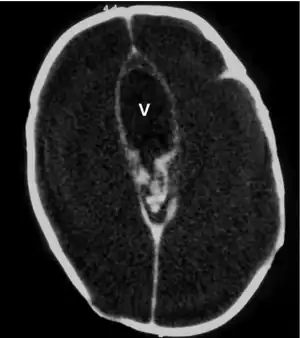

Macrocephaly is a condition in which circumference of the human head is abnormally large.[1] It may be pathological or harmless, and can be a familial genetic characteristic. People diagnosed with macrocephaly will receive further medical tests to determine whether the syndrome is accompanied by particular disorders. Those with benign or familial macrocephaly are considered to have megalencephaly.

Many people with abnormally large heads or large skulls are healthy, but macrocephaly may be pathological. Pathologic macrocephaly may be due to megalencephaly (enlarged brain), hydrocephalus (abnormally increased cerebrospinal fluid), cranial hyperostosis (bone overgrowth), and other conditions. Pathologic macrocephaly is called "syndromic", when it is associated with any other noteworthy condition, and "nonsyndromic" otherwise. Pathologic macrocephaly may be caused by congenital anatomic abnormalities, genetic conditions, or by environmental events.[3]

Macrocephaly is customarily diagnosed if head circumference is greater than two standard deviations (SDs) above the mean.[11] Relative macrocephaly occurs if the measure is less than two SDs above the mean, but is disproportionately above that when ethnicity and stature are considered. Diagnosis can be determined in utero or can be determined within 18–24 months after birth in some cases where head circumference tends to stabilize in infants.[12] Diagnosis in infants includes measuring the circumference of the child's head and comparing how significant it falls above the 97.5 percentile of children similar to their demographic. If falling above the 97.5th percentile then the patient will be checked to determine whether there is any intracranial pressure present and whether or not immediate surgery is needed.[2] If immediate surgery is not needed then further testing will be done to determine whether the patient has either macrocephaly or benign macrocephaly.